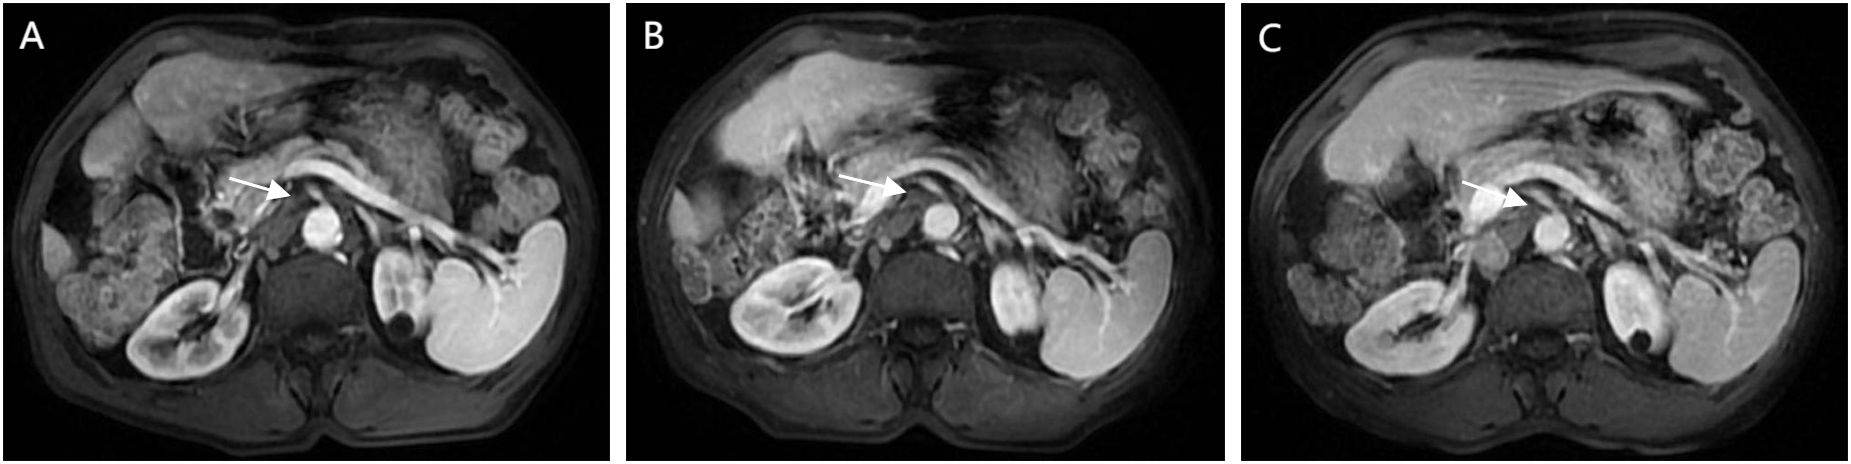

Figure 1

Figure 1. CT Findings: (A) Unenhanced CT scan. An irregular soft tissue mass in the subcapsular region of the right posterior hepatic lobe shows heterogeneous density without capsular retraction or biliary dilation. (B) Early arterial phase. Thickened arteries are seen surrounding the lesion. The mass exhibits marked heterogeneous enhancement with internal non-enhancing areas. (C) Portal venous phase. The lesion remains heterogeneously enhanced. The peripheral portion shows mild washout compared to the prior phase, while nodular enhancement emerges in the central region. (D) Delayed phase. Further peripheral washout is observed. Central nodular enhancement persists with slight decrease in intensity.

A 66-year-old male was admitted to the hospital due to the discovery of a liver tumor. One week prior to admission, the patient underwent an abdominal ultrasound during a routine physical examination, which revealed a mass in the right posterior lobe of the liver. Further contrast-enhanced CT of the upper abdomen indicated imaging features consistent with a malignant liver tumor, measuring 4.1 cm × 2.7 cm × 4.4 cm (Figure 1). The patient had a history of hepatitis C, which had been cured with antiviral therapy two years before admission. He also had a history of diabetes mellitus, currently managed with regular oral acarbose and metformin, resulting in well-controlled blood glucose levels. The patient denied other medical or family histories. Physical examination revealed no significant positive findings. Laboratory tests showed a positive hepatitis C antibody (+), while other results including complete blood count (WBC: 5.31x10 (9)/L, NEUT%: 67.5%), liver function tests (TBIL: 14.5 umol/L, ALT: 38 U/L, AST: 25 U/L, ALB:41.8 g/L), coagulation profile, renal function tests, alpha-fetoprotein (AFP: 2.92 ng/ml), protein induced by vitamin K absence or antagonist-II (PIVKA-II: 16.1 mAU/ml), and Carbohydrate Antigen 19-9 (CA19-9: 18 IU/mL) were all within normal ranges. Subsequent contrast-enhanced MRI further confirmed the presence of a malignant liver lesion, suggestive of primary HCC (Supplementary Figure 1). The patient was classified as Child-Pugh A for liver function and had an Eastern Cooperative Oncology Group (ECOG) performance status score of 0.

Regarding the imaging manifestations of SHC, a study by He et al. (9) on dynamic contrast-enhanced CT of 13 patients with sarcomatoid HCC demonstrated that the primary lesion was more frequently located in the right lobe (84.6%, 11/13) than in the left lobe. The masses were mostly irregular in shape, with 7 cases showing central ischemic necrosis. Additionally, dynamic enhanced CT in 8 patients revealed a “slow-in and slow-out” pattern, characterized by peak enhancement occurring during the portal venous phase. Similarly, Liao et al. (6) observed central necrosis with peripheral arterial enhancement in ~50% of 40 SHC cases, while only 47.5% showed typical HCC enhancement kinetics. Koo et al. (10) corroborated these atypical imaging findings. The CT findings in our patient closely resembled prior studies but with slight differences, and demonstrated notable distinctions from the imaging manifestations of conventional HCC. Notably, the tumor exhibited significant central necrosis along with intratumoral enhancement during the arterial phase. Crucially, persistent enhancement was observed in the central region of the tumor during both the portal venous and delayed phases, presenting an early enhancement with late washout pattern (early-in and late-out), without the complete peripheral washout characteristic of conventional HCC. This atypical enhancement pattern may reflect the rapid growth biology of SHC (9).